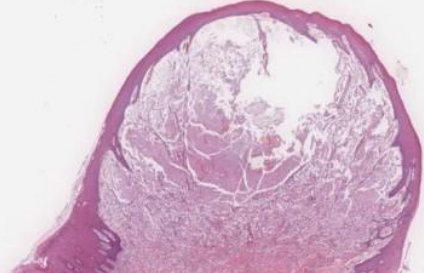

| Branchial Cleft Cyst (cervical lymphoepithelial cyst,鰓裂囊) |

branchial arches 殘留 (2nd,95%) | SCM 前/下 |

10 - 40y | 複層鱗狀、淋巴、發中心(germinal center)。 |